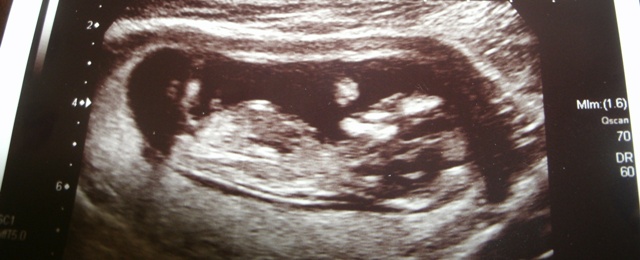

HUSBAND SAYS PINK I SAY BLUE

Hmmm....I'd say :bigboy: , but I'm not 100% sure.

Looks :bigboy: to me.

I'd guess Boy, goodluck.

I don't see a nub skull look boyish maybe? GL!